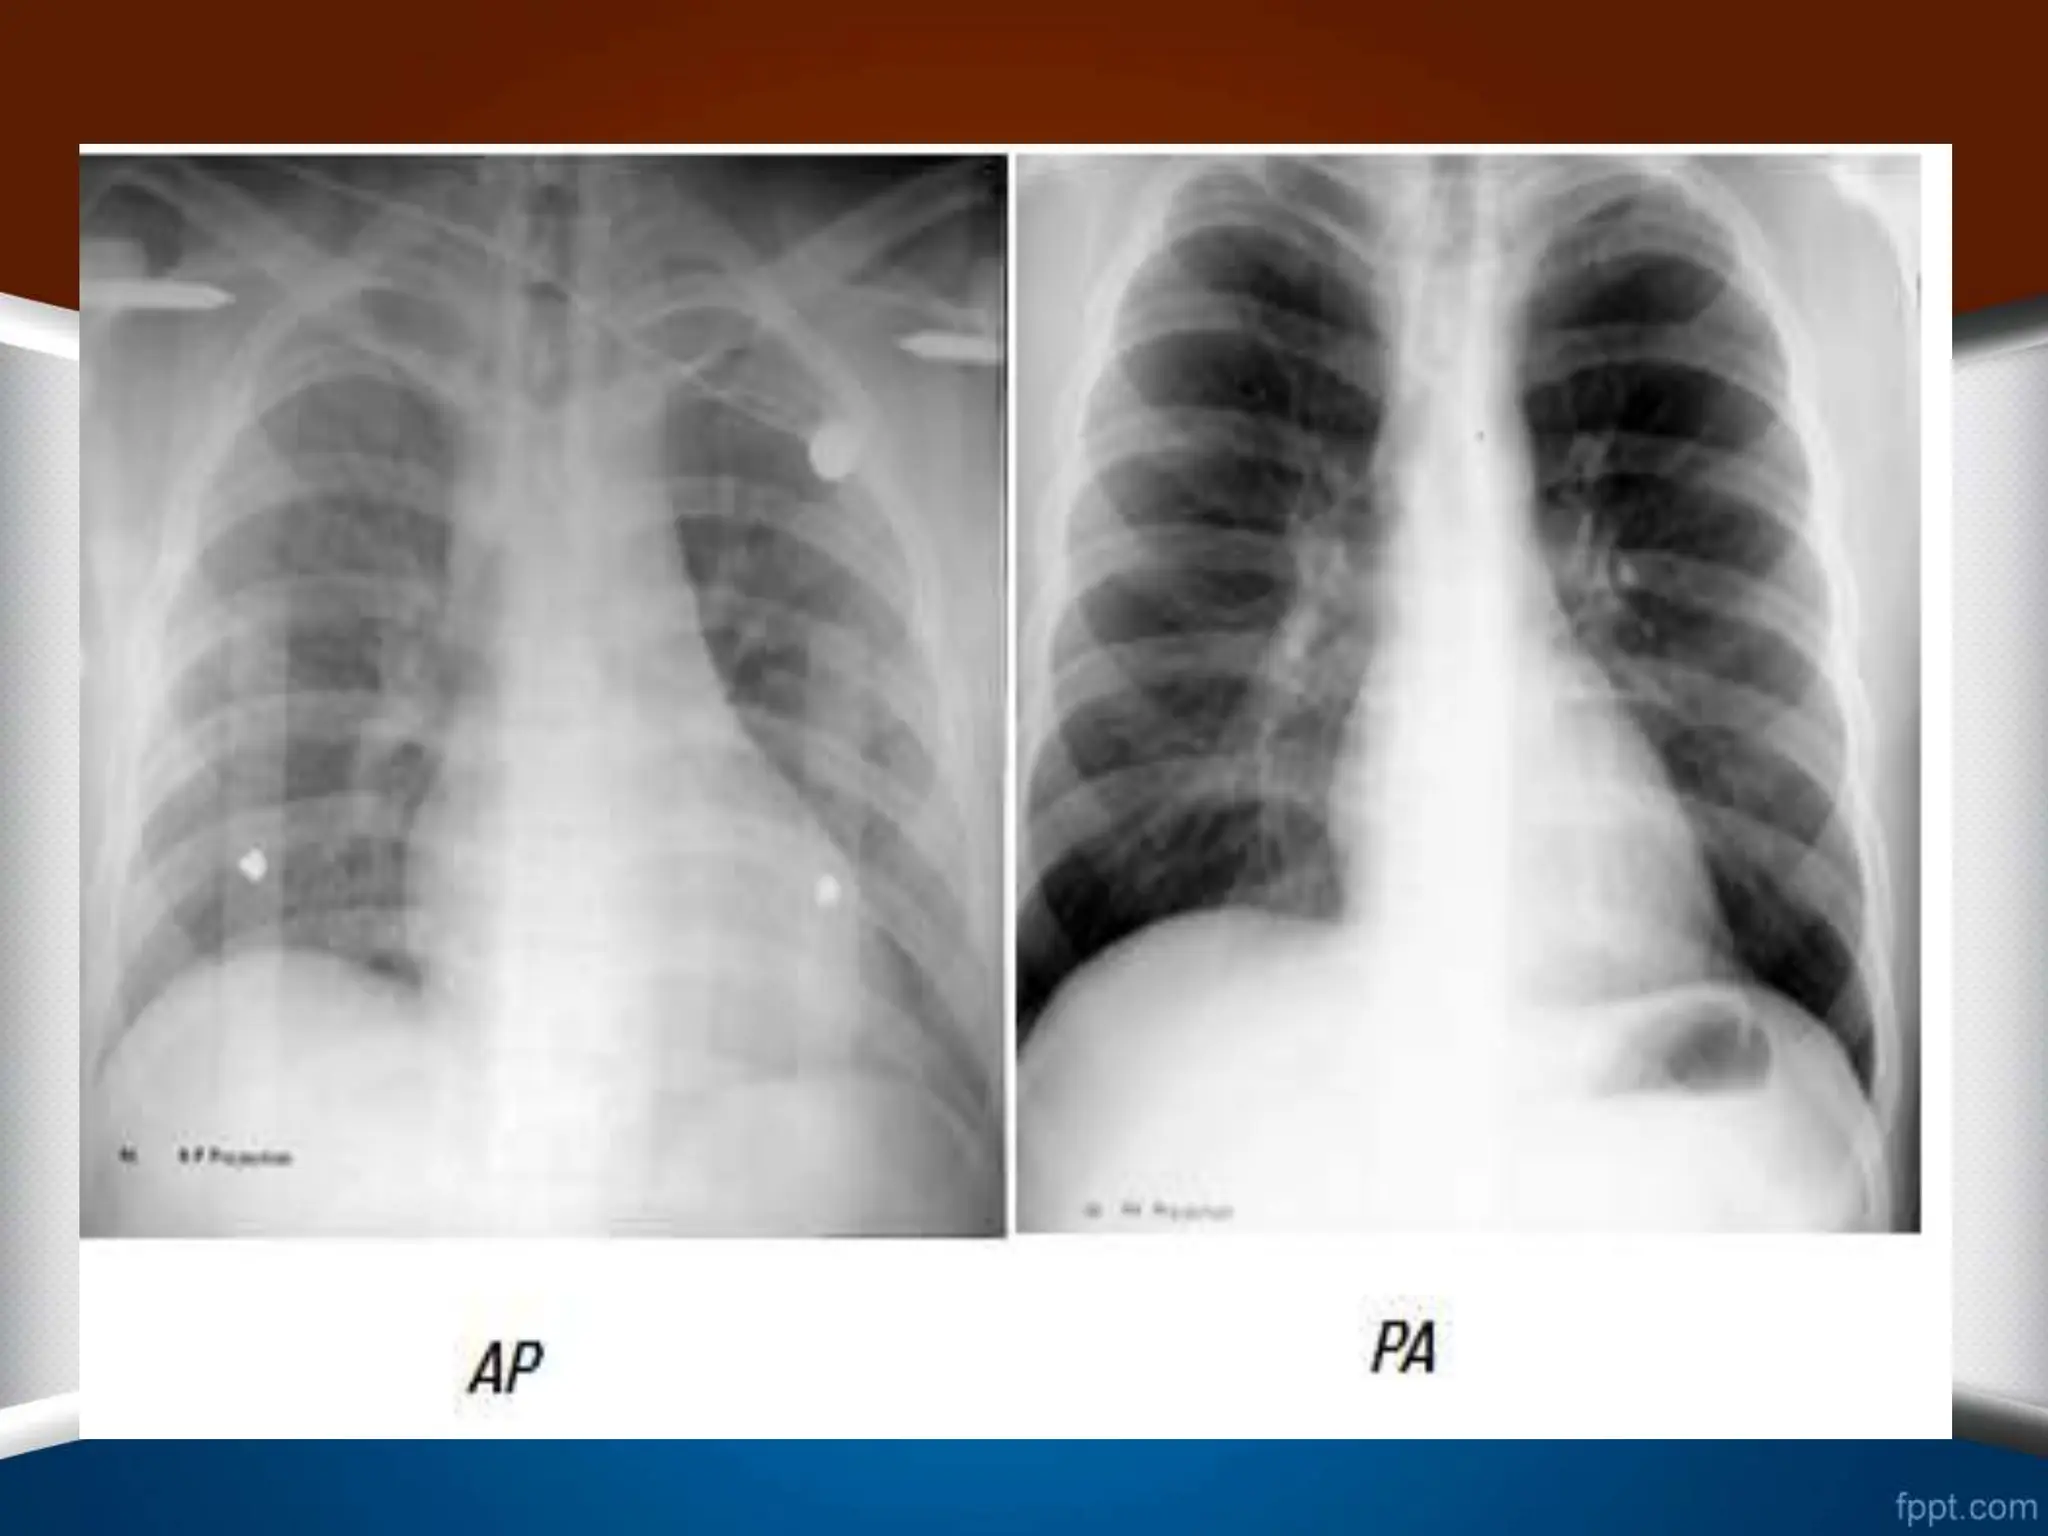

AP or PA

•

4

-

‫فیلم‬ ‫در‬ ‫اسکاپوال‬

PA

‫است‬ ‫دور‬ ‫ریه‬ ‫فیلد‬ ‫از‬

.

5

‫گرافی‬ ‫در‬

AP

‫اشعه‬ ‫تیوب‬ ‫و‬ ‫شده‬ ‫گرفته‬ ‫پرتابل‬ ‫صورت‬ ‫به‬ ً‫ال‬‫معمو‬ ‫که‬

X

‫نزدیک‬ ‫بیمار‬ ‫به‬

‫تر‬

‫حاشیه‬ ،‫است‬

‫هستند‬ ‫محوتر‬ ‫ها‬

6

‫مهره‬ ‫انتهای‬ ‫صفحه‬

‫گرافی‬ ‫در‬ ‫که‬ ‫حالی‬ ‫در‬ ‫هستند‬ ‫مشخص‬ ‫واضح‬ ‫طور‬ ‫به‬ ‫ها‬

‫دارند‬ ‫المینیت‬ ‫حالت‬

• ‫معیارهای‬ AP or PA • 1 - ‫رادیوگرافی‬‫در‬ PA ‫رؤیت‬ ‫قابل‬ ‫چپ‬ ‫دیافراگم‬ ‫زیر‬ ‫و‬ ‫فوندوس‬ ‫ناحیه‬ ‫در‬ ‫معده‬ ‫گاز‬ ً‫ال‬‫معمو‬ ‫است‬ ( ‫است‬ ‫شده‬ ‫گرفته‬ ‫ایستاده‬ ‫حالت‬ ‫در‬ ‫عکس‬ ‫این‬ ‫که‬ ‫چرا‬ ) ‫گرافی‬ ‫در‬ ‫که‬ ‫صورتی‬ ‫در‬ AP ‫که‬ ‫می‬ ‫گرفته‬ ‫خوابیده‬ ‫حالت‬ ‫به‬ ً‫ال‬‫معمو‬ ‫نمی‬ ‫رؤیت‬ ‫گاز‬ ‫این‬ ‫شود‬ ‫شود‬ . • 2 - ‫گرافی‬ ‫در‬ PA ‫می‬ ‫رؤیت‬ ‫کالویکل‬ ‫باالی‬ ‫در‬ ‫ریه‬ ‫قله‬ ‫تصویر‬ ‫در‬ ‫که‬ ‫حالی‬ ‫در‬ ،‫شود‬ AP ‫قابل‬ ‫نمی‬ ‫رؤیت‬ ‫باشد‬ . • 3 - ‫کالویکل‬ ‫درگرافی‬ ‫ها‬ PA ‫تح‬ ‫دیستال‬ ‫در‬ ‫و‬ ‫دارند‬ ‫باال‬ ‫سمت‬ ‫به‬ ‫تقعر‬ ‫پروگزیمال‬ ‫قسمت‬ ‫در‬ ‫دب‬ ‫گرافی‬ ‫در‬ ‫که‬ ‫حالی‬ ‫در‬ ‫دارند‬ ‫باال‬ ‫به‬ ‫رو‬ AP ‫نیست‬ ‫گونه‬ ‫این‬ . • 4 - ‫فیلم‬ ‫در‬ ‫اسکاپوال‬ PA ‫است‬ ‫دور‬ ‫ریه‬ ‫فیلد‬ ‫از‬ . • 5 - ‫گرافی‬ ‫در‬ AP ‫اشعه‬ ‫تیوب‬ ‫و‬ ‫شده‬ ‫گرفته‬ ‫پرتابل‬ ‫صورت‬ ‫به‬ ً‫ال‬‫معمو‬ ‫که‬ X ‫نزدیک‬ ‫بیمار‬ ‫به‬ ‫تر‬ ‫حاشیه‬ ،‫است‬ ‫هستند‬ ‫محوتر‬ ‫ها‬ . • 6 - ‫گرافی‬ ‫در‬ AP ‫مهره‬ ‫انتهای‬ ‫صفحه‬ ‫گرافی‬ ‫در‬ ‫که‬ ‫حالی‬ ‫در‬ ‫هستند‬ ‫مشخص‬ ‫واضح‬ ‫طور‬ ‫به‬ ‫ها‬ PA ‫دارند‬ ‫المینیت‬ ‫حالت‬ .